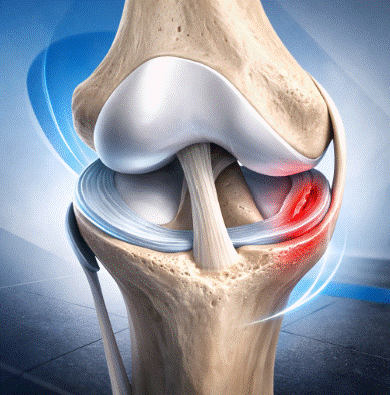

Tendinopatía rotuliana en deportistas: tratamiento y evidencia

La tendinopatía rotuliana en deportistas es una de las lesiones por sobrecarga más frecuentes y limitantes en los deportes que implican saltos repetitivos, como el baloncesto, el voleibol, el atletismo de saltos o el fútbol. Conocida popularmente como «rodilla del saltador», esta patología afecta al tendón rotuliano en su inserción en el polo inferior de […]